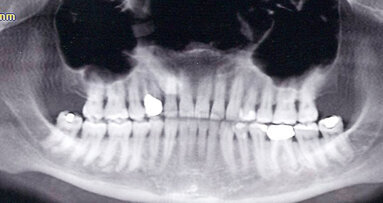

Uno studio rivela che la disfunzione temporo mandibolare (TMD) è significativamente più diffusa tra coloro che praticano le arti marziali da professionisti rispetto agli amatori.

Nel complesso, la prevalenza di TMD è stata più alta tra i professionisti, mentre era ad un livello similare tra gli amatoriali e quelli che non praticano questa disciplina.

Mentre circa il 54 per cento dei professionisti del karate e quasi il 62 per cento dei praticanti di arti marziali miste hanno avuto una qualche forma di TMD, la disfunzione è stata diagnosticata solo nel 14 per cento circa degli amatoriali e dei non atleti.

Secondo la ricerca, la diagnosi di artralgia discale è stata più frequente tra i professionisti (46 per cento) e nei praticanti di arti marziali miste (39 per cento) rispetto ai non atleti (7 per cento).

Intitolato “Professional karate-do and mixed martial arts fighters present with a high prevalence of temporomandibular disorders” e pubblicato online il 29 ottobre sul the Dental Traumatology prima della stampa, lo studio è stato condotto all'Università federale del Paraná, in collaborazione con i ricercatori della Positivo University e della Pontifícia Universidade Católica di Paraná (Brasile).